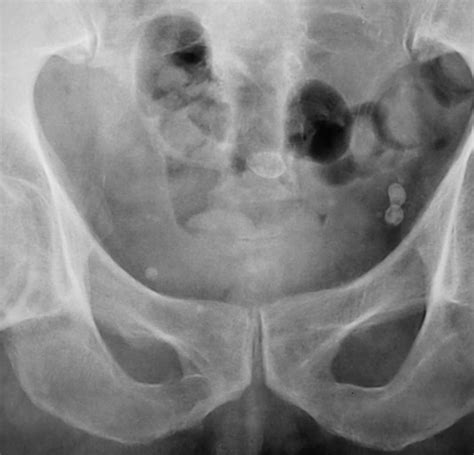

Пациент направлен на рентгенографию костей таза...